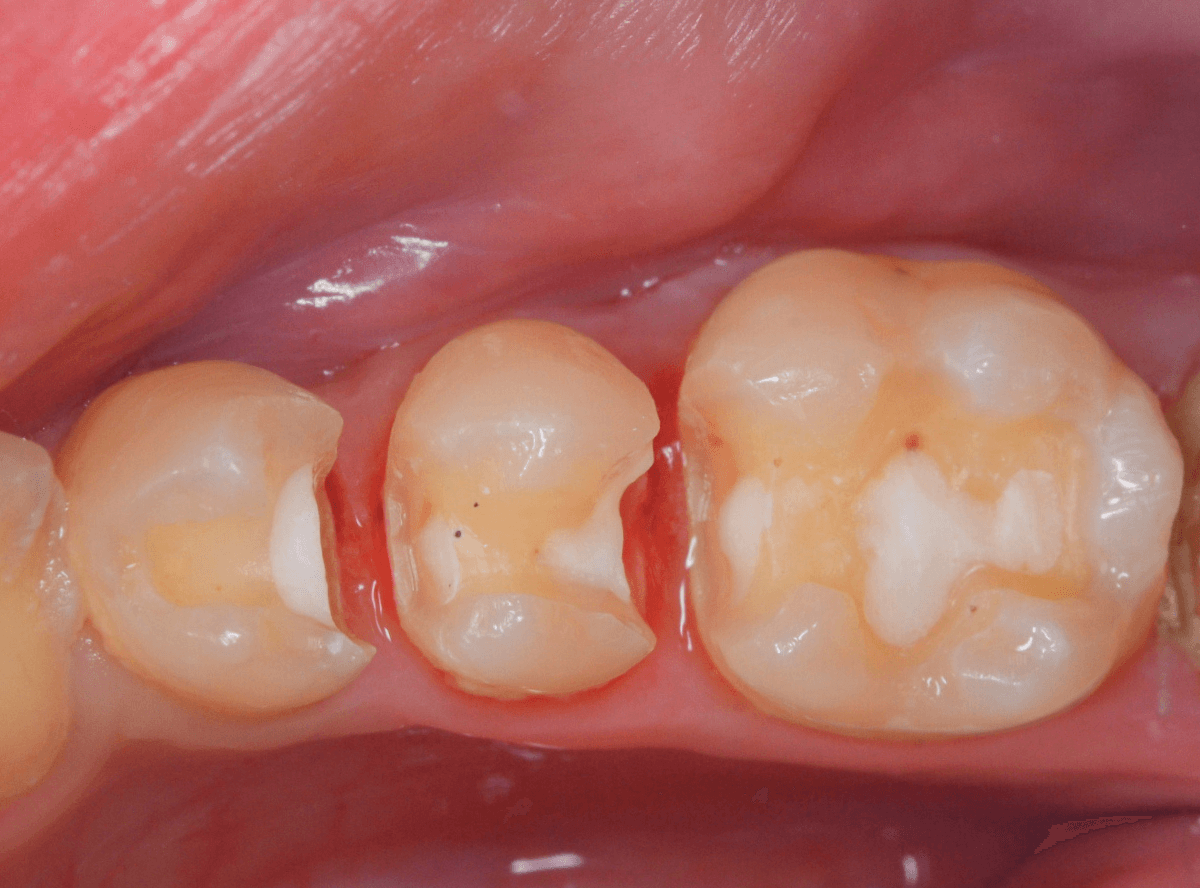

虫歯を治療して、セメントで歯を削った部分を封鎖した後、再修復を検討中で、半年以上来院されなかった患者さんです。

虫歯を治療して、セメントで封鎖した状態というのは、家でいえば、しっかりした屋根がない状態です。

今回は、セメントの一部がはがれる程度で済んでいましたが、虫歯が再発し、再治療、最終修復物の変更の可能性も出てきます。

治療再開後、セラミックの最終修復を希望されましたので、歯をトリミングし、型取りします。

治療後の状態です。